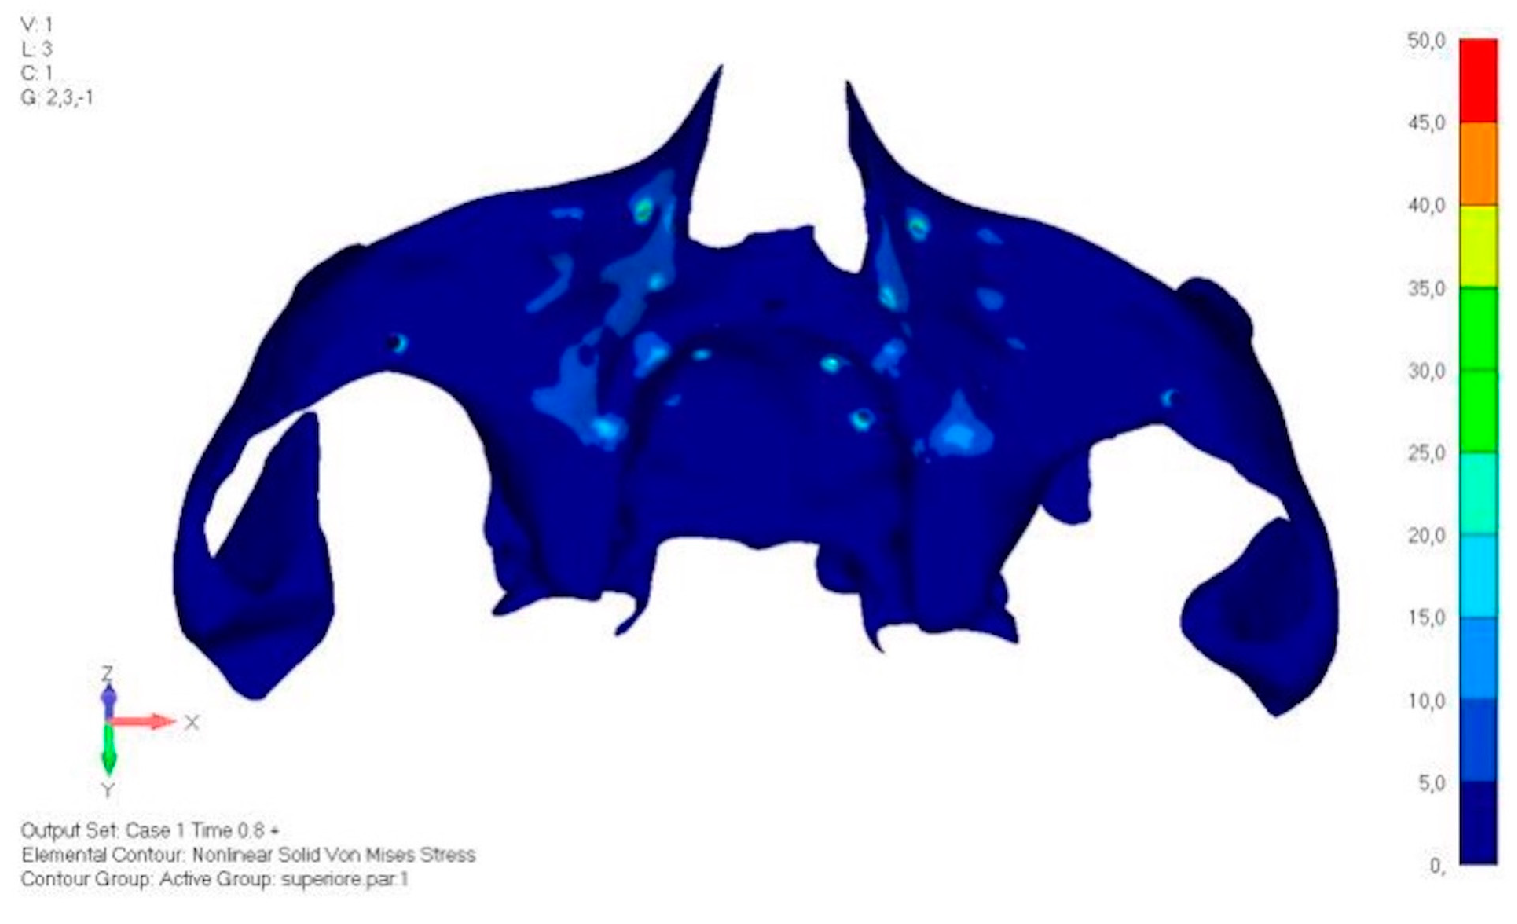

- Model V0. From the analysis of Model V0, it emerged that the most critical situation is related to load configuration 3 (Figure 5a,b), which represents a load applied to the anterior right side. The least critical situations are load configurations 1 and 2 (Figure 6 and Figure 7), corresponding to a load distributed across the entire dentition and a load distributed only on the posterior teeth, respectively. Regarding the stress values observed, no critical issues were identified with the juxta-osseous implant. In load configuration 3, the stresses are below the breaking limits of titanium laser melting: peak stresses of 500 MPa are reached only in very localized areas of the implant.

- Model V1. Added posterior screws, reducing stress on anterior parts and achieving more balanced distribution. The addition of the posterior screw has certainly alleviated the load on the palatal screw, which was excessively stressed in the previous model (Figure 8). The screw now experiencing the most stress is the posterior screw: compared to the previous case, only part of the hole shows a stress exceeding 50 MPa, and the area affected by this stress is therefore much more contained (Figure 9a,b).